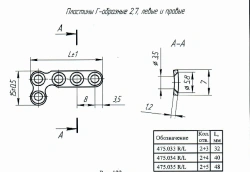

L-Shaped Implant Plate 2.7, Code 475.035R/L

US$90-300

Length:

48

Material:

Titanium alloy

OSTEOMED-M LLC 🇷🇺

L-Shaped Implant Plate 2.7, Article 475.034R/L

US$90-300

Length:

40

Material:

Titanium alloy

OSTEOMED-M LLC 🇷🇺